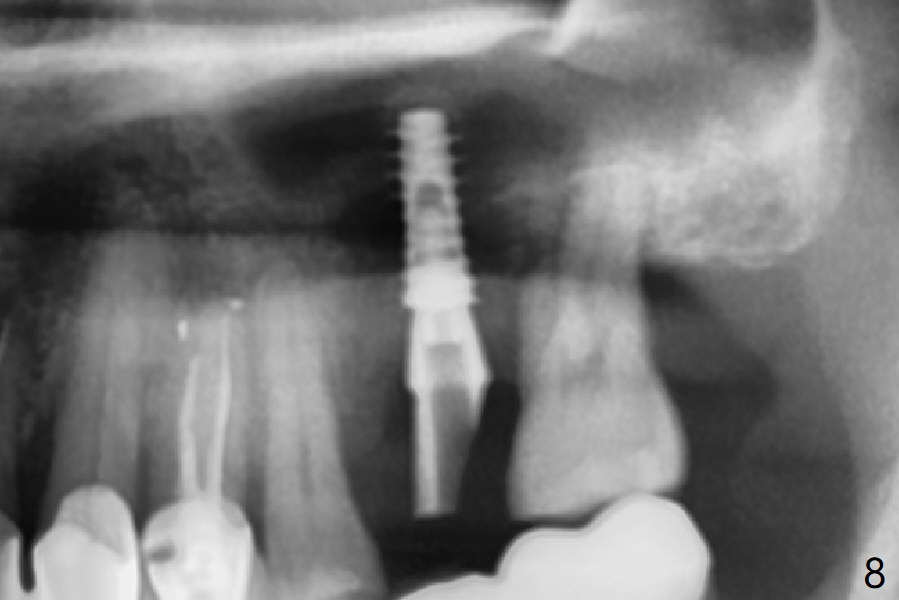

Osteotomy is initiated with Magic Split and 3 mm Magic Expander (ME, flapless) nearly 3 months post socket preservation. To improve the trajectory, the ME is redirected (Fig.1 red line). After use of 3.8 mm ME, Vanilla Graft is placed in the buccal and mesial aspects of the osteotomy. Following reuse of 3 and 3.8 mm MEs, a 4x11 mm dummy implant is inserted with stability (Fig.2 (*: allograft)). More of allograft is placed prior to placement of 5x11 mm IBS implant (Fig.3,4 (~30 Ncm)). The latter is placed palatal. Last the allograft is placed palatal. A 5x4(2) mm abutment is placed to hold periodontal dressing in place. When the ridge is narrow, the implant should be small; 4 mm probably the most appropriate in this case. There is a buccal gap 2 weeks postop (i.e., after dislodgement of periodontal dressing, Fig.5). The implant and abutment appear to be loose ~ 1.5 months postop. The pair abutment is changed to a healing one (5x3mm). The implant seems to be osteotointegrated 3.5 months posotp (Fig.6). Because of the mesial shift of the tooth #15 (Fig.6 arrow (6 months post #14 extraction; anterior open bite)), an angled abutment (5x4mm, 15 degree) is used (Fig.7). Limited orthodontic treatment has to be initiated because the mesially shifted #15 has no occlusal contact mesially (Fig.7 *). A provisional is fabricated with light supra-occlusion. A separator is placed between #14 and 15. Once a space is created in a week, acrylic is added to the distal surface of the provisional and the separator is re-used. In fact the implant is found to be unstable 4.5 months postop (Fig.8,9). The palatal (P) plate is thin and incomplete. The provisional is reduced infraocclusal. Two months the implant remains unstable and is removed.